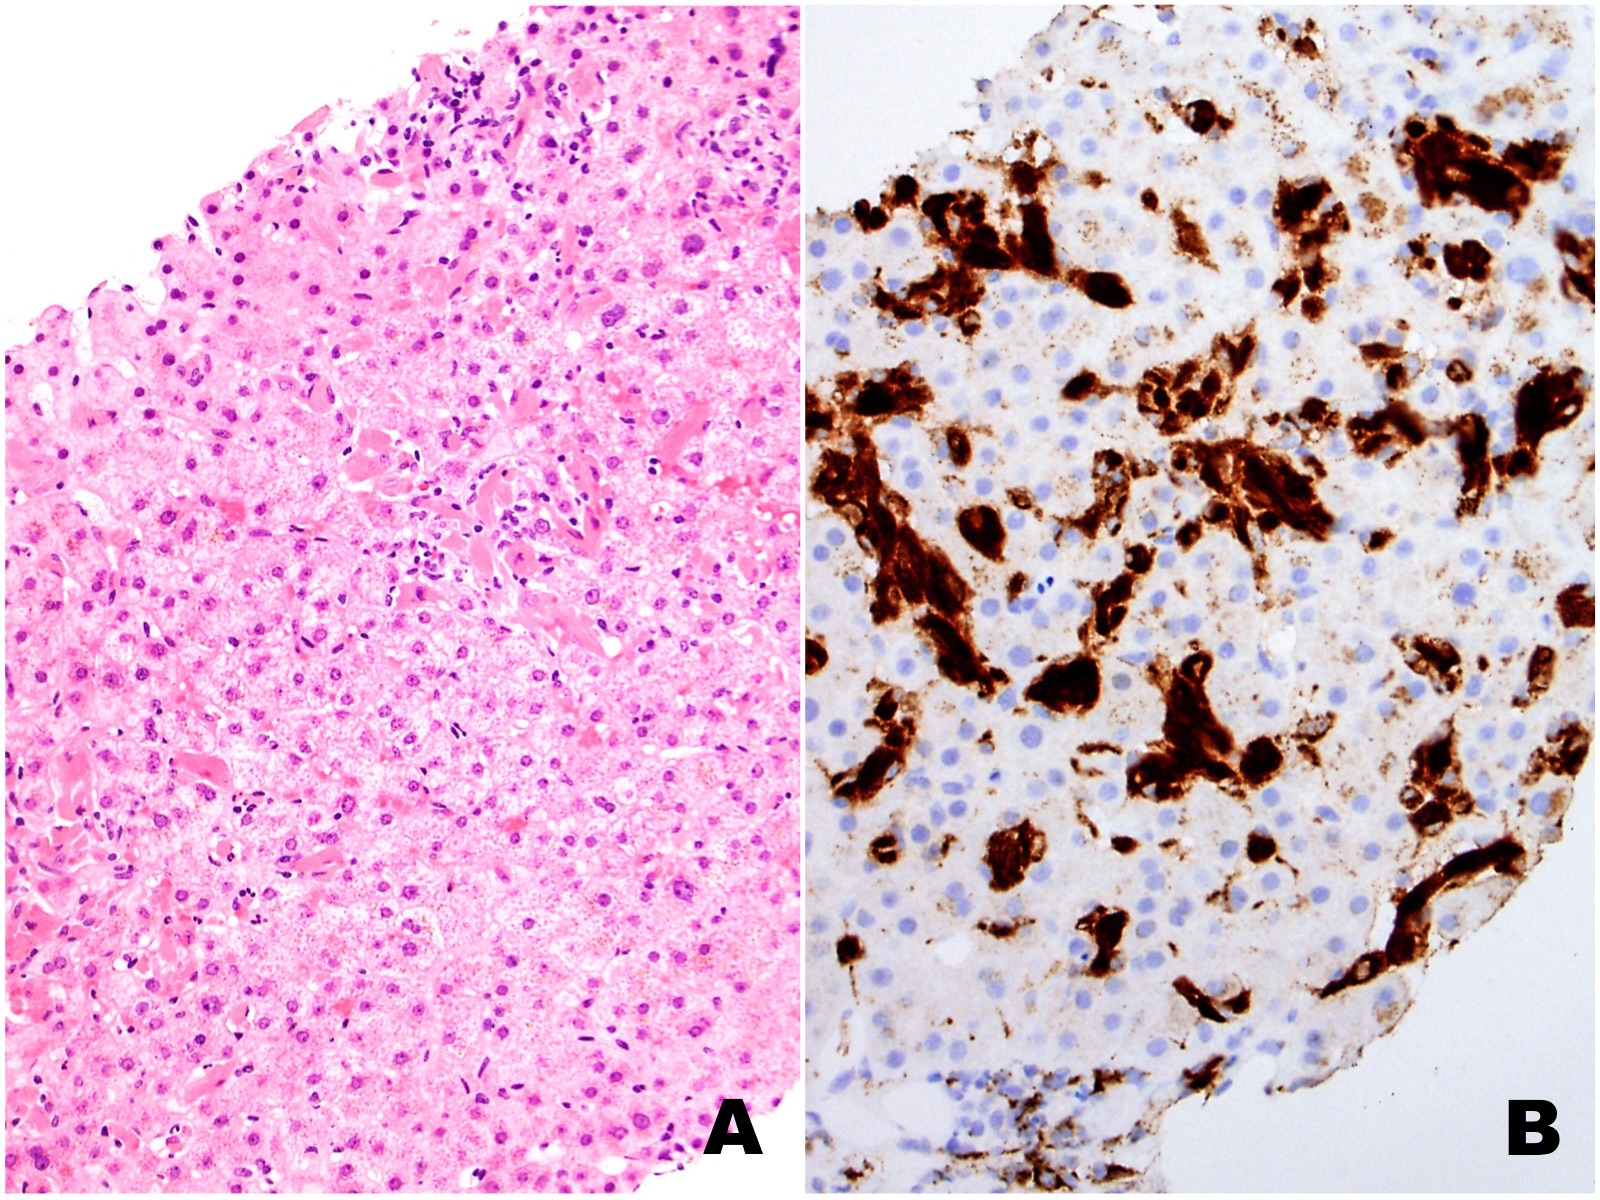

The liver biopsy shows extensive sinusoidal infiltration by bland appearing plump eosinophilic cells with somewhat retractile or granular cytoplasm (Figures 1A and 2A). These cells are positive for CD68 confirming they are histiocytes (Figures 1B and 2B). The histiocytes contain crystalline immunoglobulin kappa highlighted on the Ig kappa and PAS-D stains (Figures 3A and 3B, respectively). Ig lambda was negative.